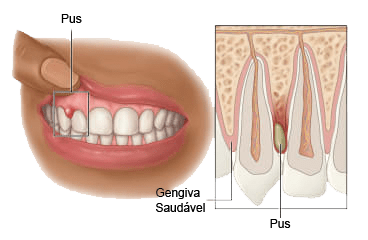

🚨 Urgência — não esprema

🚨 Urgência — não esprema

O que é: Abscesso periodontal ou fístula — uma coleção de pus por infecção ativa da gengiva ou da raiz. A "bolinha" que "estoura e passa" volta enquanto a infecção não for tratada.

O que fazer: Avaliação urgente. Não perfure, não esprema. O tratamento envolve drenagem pelo periodontista, raspagem da bolsa e em alguns casos antibiótico como adjuvante.